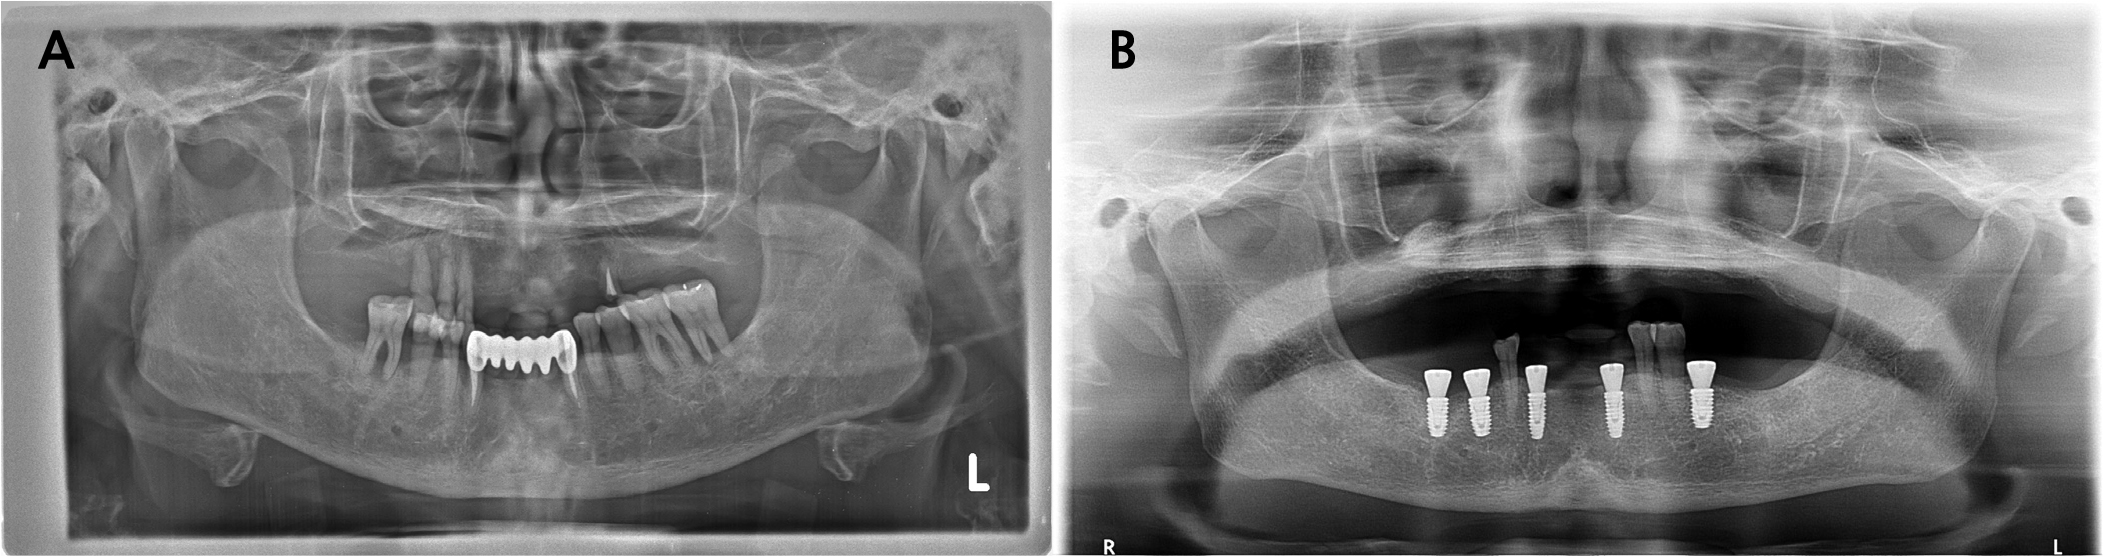

A 62-year-old female presented to the Department of Periodontology in Dankook University Dental Hospital with complaints of tenderness and a fever-like sensation around implant #43. A sinus tract was noted at the mesial aspect of the buccal peri-implant mucosa. Pocket probing depth ranged from 1–3 mm without bleeding. Panoramic and intraoral radiographs, along with cone-beam computed tomography (CBCT), showed intact crestal bone, a periapical radiolucency mainly involving the buccal aspect and extending lingually, and a thinned buccal bone with a 2 mm fenestration (Fig. 1). Adjacent tooth #44 responded normally to cold and electric pulp tests. The patient had a history of rheumatoid arthritis and allergies to sulfonamides and Penicillin. Her dental history included root canal treatment on #43, extractions owing to advanced bone loss (#15–13, 24, 33, 36, 37, 43, 45, 46), and implant treatment performed 1.3 years earlier using static computer-assisted surgery (Neo NaviGuide; Neobiotech, Wonju, Korea) (Fig. 2). A provisional diagnosis of RPI was made. A reconstructive surgical approach via the buccal aspect was planned.